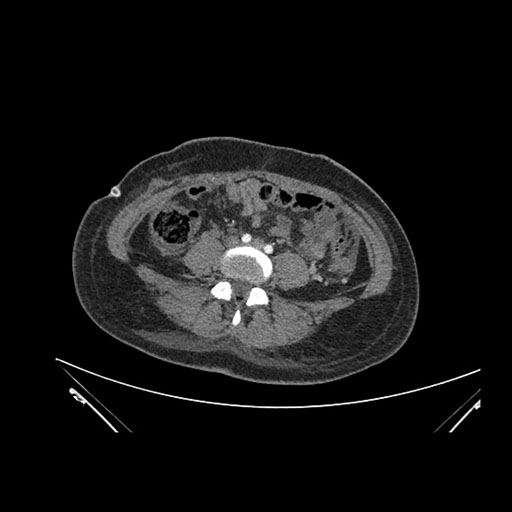

Axial Venous